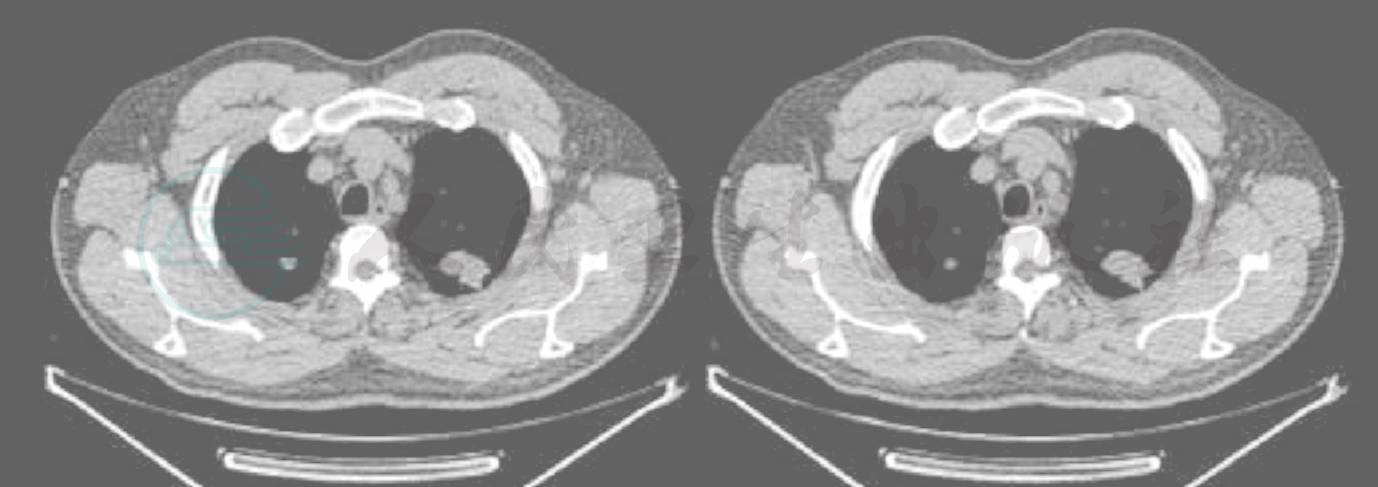

图2 高分辨CT纵隔窗横断面

左肺上叶结节内见小低密度影及点状钙化影,平均CT值约为34.5Hu,右肺结节内见点状低密度灶及高密度影,结节周围见散在斑点状高密度影